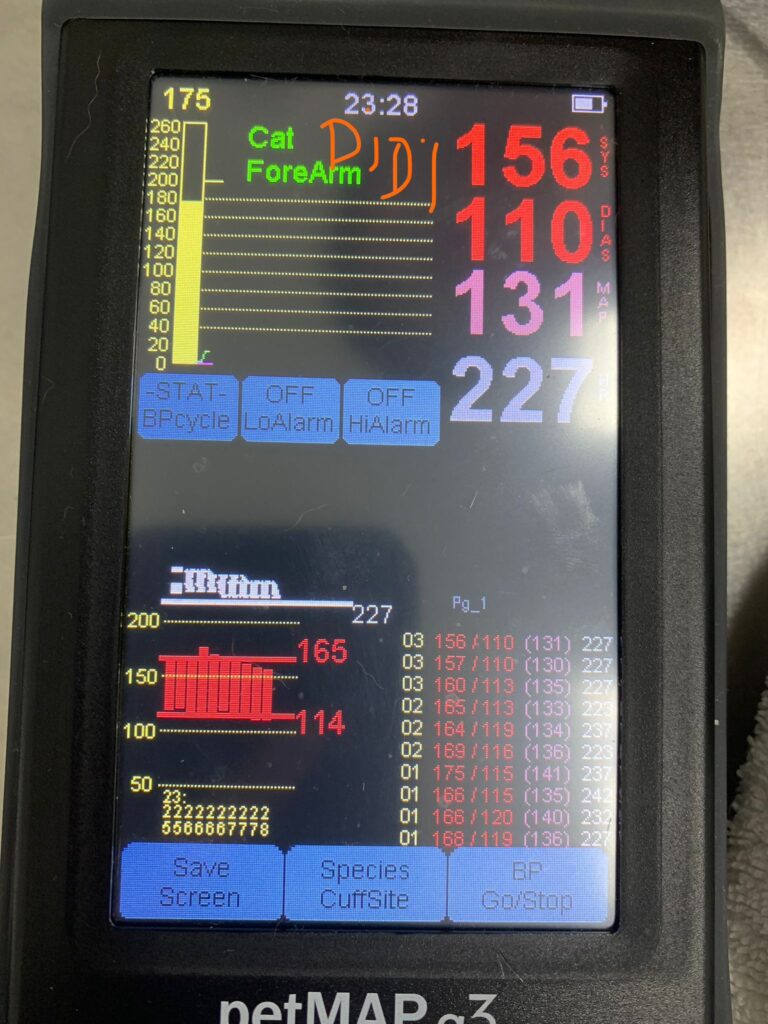

Can hear gallop rym – consistent w the hr taken 204. Bp average 191. But clinic damn noisy cos of hacking sound above.when the sound stop rehear again, the heart ok. Anyway last time taken pro bnp le, negative.

Taken bp using from right leg.

His bp at resting is abnormality high. But can due to heart, kidney or ???

So what’s the med he needs to be on for his high bp?

*9. Repeat BP as well while on doxy and bupre, hypertension may be due to pain/anaemia*